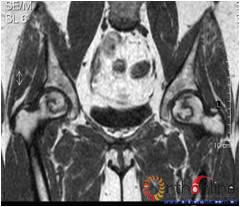

2.2 影像学结果 影像学结果与临床结果基本同步。临床结果优的36髋,34髋维持圆形且修复较完全(图1)。1例双髋Ⅲa激素性(SARS患者)ONFH,术后随访7年8月,X线片显示股骨头虽不圆,但临床HHS评分90分为优(图2)。功能为良的12髋,7髋股骨头不圆,但股骨头与髋臼匹配好,其余5髋股骨头维持圆形。临床评定为差的17髋,股骨头均有超过4mm塌陷,股骨头与髋臼匹配不好,股骨头内无折断,MRI未显示骨髓水肿,关节间隙呈不对称改变,CT扫描示软骨下骨折,MRI显示骨髓水肿。

图2 男,22岁,激素性骨坏死,(1)双侧股骨头骨髓水肿,ARCO分期Ⅲa期,C3型;(2)X线片示股骨头塌陷,术前关节功能差(Harris评分50分);(3)打压植骨术(未加BMP2)后7年,关节功能好(Harris评分90分),股骨头有轻度塌陷,但头臼匹配好;(4)蛙式位显示股骨头臼匹配好